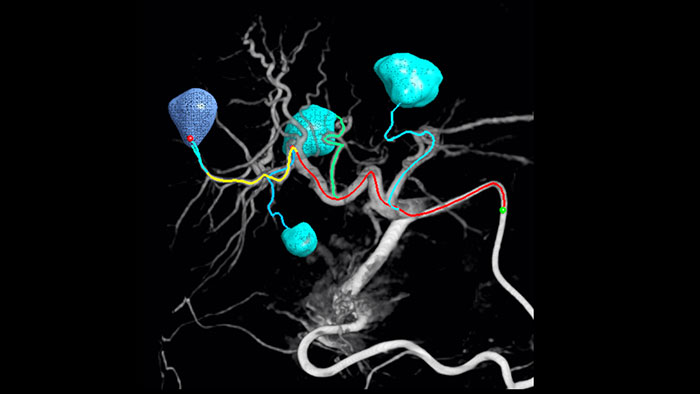

Detección automática del alimentador con EmboGuide

EmboGuide

La adopción de técnicas de quimio/radioembolización como la QET y la Radioterapia interna selectiva (Selective Internal Radiotherapy, SIRT) impulsa la necesidad de estandarización y eficiencia. Caso tras caso, debe localizar de manera confiable y uniforme los tumores, identificar todos los vasos nutricios y planificar/llevar a cabo el enfoque intervencionista apropiado.

Nuestra solución de Detección automática de alimentadores puede mejorar, de manera significativa, la detección de arterias nutricias en comparación con la TC de haz cónico sola.  EmboGuide le ayuda a maximizar la eficacia de sus procedimientos de QET, ya que potencialmente mejora su sensibilidad, reduce los falsos positivos y maximiza la concordancia entre lectores.1

86 %

Sensibilidad2

57 %

menos falsos

positivos2

99,7 %

Concordancia

entre lectores2